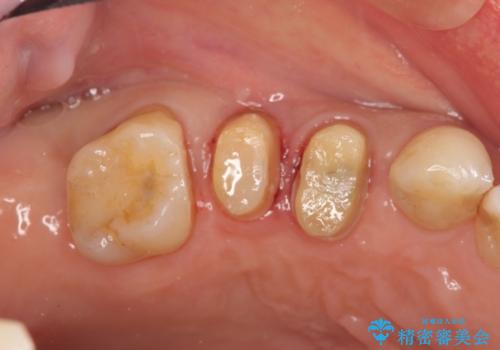

特定の歯に強く力がかかりまた歯周病により臨床歯根が短くなっているような場合、歯の動揺を抑えるため連結補綴が検討されます。

歯の動揺が続くとより周囲の骨を失い最終的には歯を喪失してしまう可能性が高くなってしまうためです。

今回連結補綴を行うにあたり、歯周病の問題を解決するために再生療法・歯周ポケット除去手術を、またより歯の神経を保存し力に対抗できる環境を整えるために小矯正を行い精度の高いメタルボンドクラウンを製作することができました。